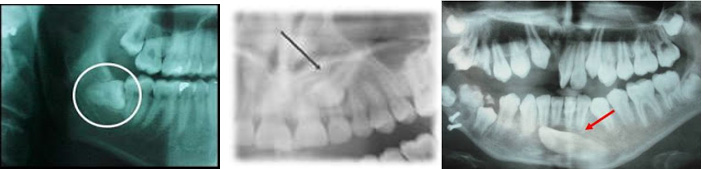

Los terceros molares inferiores están relacionados con los fuertes dolores de cabeza, así también con el corazón, para ello cuando nuestro paciente presenta un cuadro agudo de migraña nosotros podemos realizar la prueba del Test de Huneke; éste método se desarrolla por la aplicación de procaína, lo cual en un principio se dio a conocer como anestesia curativa, su verdadero significado lo obtuvo gracias al fenómeno en segundos de HUNEKE, se habla de un fenómeno en segundos cuando después de aplicar inyección en el campo interferente antes llamado foco, en éste caso el tercer molar retenido o semi retenido; se logra eliminar el dolor de cabeza instantáneamente sus efectos a distancia siempre y cuando que ese efecto de alivio, perdure por un determinado tiempo.

Con esto se abrieron caminos totalmente nuevos en la observación de las llamadas enfermedades focales, a través de este fenómeno se pudo establecer la relación entre un determinado mal y su posible origen; como se ha indicado el terreno máxilo mandibular juega un importantísimo papel en el suceso del campo interferente, la estrecha colaboración entre el médico y el odontólogo, es indispensable y se debe establecer un cuadro completo del estado radiológico de toda la boca del paciente inclusive de todos los espacios edéntulos; pudiendo ser una alternativa al tratamiento de la cefalea la exodoncia de los terceros molares.

- Todos los dientes ectópicos, impactados o fuera de su sitio normal

Todo diente con pulpa necrótica puede tener un foco, muestre o no la radiografía alteraciones óseas en su entorno.